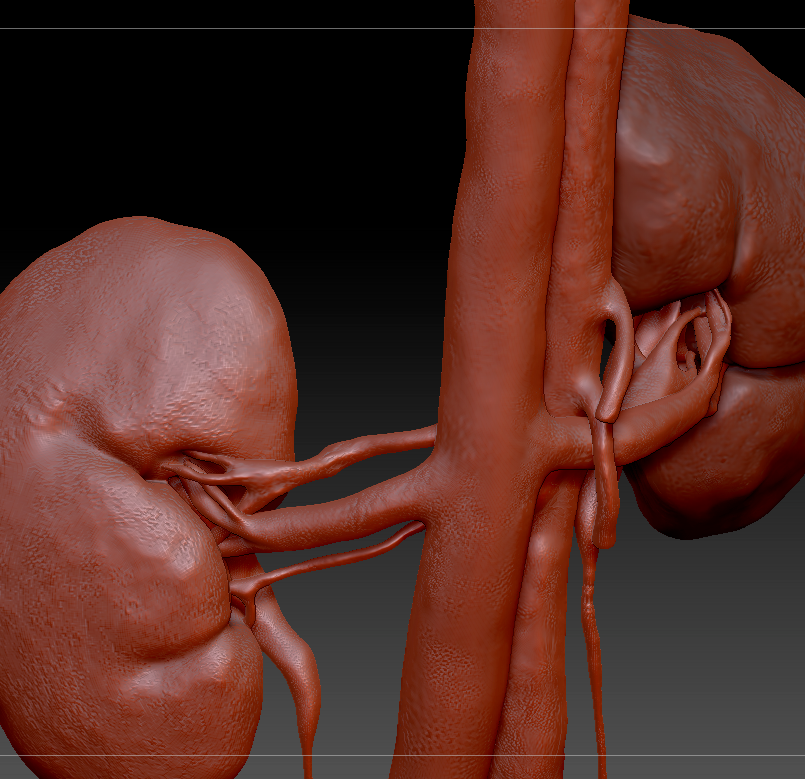

Kidney mesh reconstructed in ZBrush

Clean up the Mesh

Next the Kidney mesh is brought into a program like ZBrush where the basic mesh is reconstructed, and any missing anatomy, such as the ureters, are added to the model. Here simpler geometry is built.